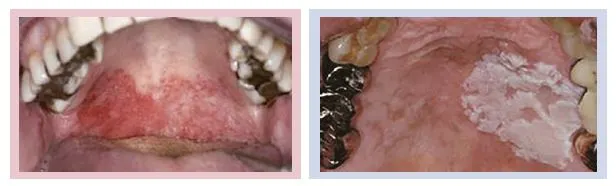

구강암 진행 전 단계의 병소를 전암병소라 부른다. 전암병소는 아직 암은 아니지만 암으로 갈 수 있는 가능성이 있는 상태를 말한다. 구강암으로 진행할 수 있는 병변을 적색, 백색병변으로 나누어 알아보자.

먼저 적색병변 은 우리가 홍반증이라 부르는 것으로 구강점막의 각화층이 떨어져 나가 생기는 것이다. 정상점막이라면 약 2-3주의 기간을 거치면 새로운 각화층으로 대체되어야 하는데 그렇지 못하고 지속된다면 세포이상을 의심해 보아야 한다. 약 14%에서 많게는 50% 정도 구강암으로 진행될 수 있다.

두 번째로는 백반증으로 불리는 백색병변 이다. 각화층이 떨어져 나가지 않고 계속 생성되면서 두꺼워지는 것으로, 앞서 홍반증보다는 낮지만 약 1%에서 15% 정도는 구강암으로 진행될 수 있기에 정기적으로 유심히 관찰해야 한다.

또한 이 두 가지가 같이 나타난 경우도 있다. 이렇게 홍반증과 백반증이 같이 나타나는 경우는 구강암으로의진행 가능성이 더 높아지므로 더 세심한 관찰이 필요하다.

구강 내 적색, 백색병변 중 불균일한 성상을 가지고 여러 병변들이 혼재되어 있고 진하고 두꺼워 보일 시 구강암이 의심스러운 병변으로 생각할 수 있겠다. 이 경우 주기적인 관찰을 통해 구강암으로의 진행 가능성이 있다고 판단되면 예방적 제거를 해주게 된다.

구강암 -06.JPG 사진3구강내 발생하는 전암병소,적색병변과 백색병변